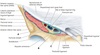

Name muscles A and B

A - Adductor brevis

B - Adductor magnus